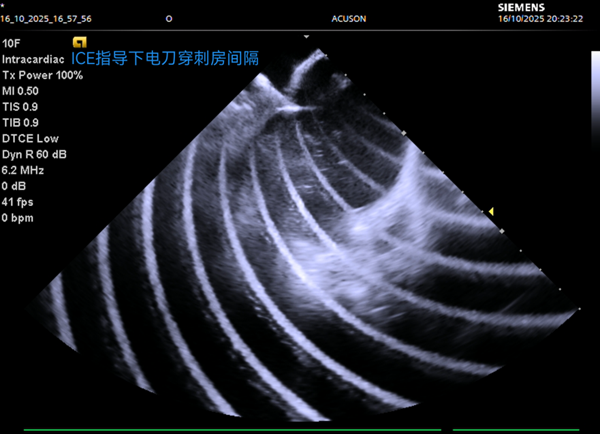

官方微信

手術(shù)團隊對兩名藏族患者進行了精準治療,其中一位52歲房顫患者,在ICE引導(dǎo)下完成左心房建模與肺靜脈隔離,全程零射線;另一位49歲患者成功轉(zhuǎn)復(fù)正常心律。

湯陽副主任醫(yī)師介紹:“房顫在高原地區(qū)高發(fā),傳統(tǒng)治療受限于設(shè)備與技術(shù),患者常面臨輻射風(fēng)險和手術(shù)痛苦。此次引進的零射線電刀穿刺技術(shù),結(jié)合三維建模與實時心包監(jiān)測,不僅精準安全,更大幅減輕了患者不適,為高原地區(qū)房顫治療提供了可靠的新路徑”。